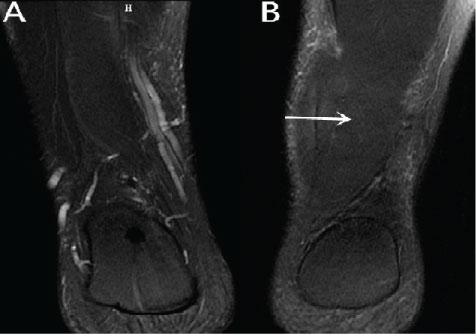

The MRI examination was performed using a 1.5-T MRI unit Signa Advantage Horizon; GE Medical Systems, Milwaukee, WI, USA. The T1 weighted coronal sequences showed the mass originating from the ventral portion of the normal soleus muscle and inserting to the medial surface of the calcaneus independently of Achilles tendon (Figure 1). Compared with the normal side, the affected side showed a homogeneous soft tissue mass located posteromedial to the flexor hallucis longus tendon and anteromedial to the Achilles tendon in all sequences (Figure 2, Figure 3 and Figure 4). It showed iso intense signal on all sequences (Figure 2, Figure 3 and Figure 4). And the pre-Achilles' fat pad was compressed by this muscle mass. The T1-weighted sequences showed a thin rim of adipose tissue within the fascial plane around the mass (Figure 1).

Figure 3: Fast spin echo T2 weighted fat-suppressed coronal images sequences show the differences between the both sides. View Figure 3

Figure 4: Fast spin echo T2 weighted fat-suppressed sagittal images show the differences between the both sides. View Figure 4